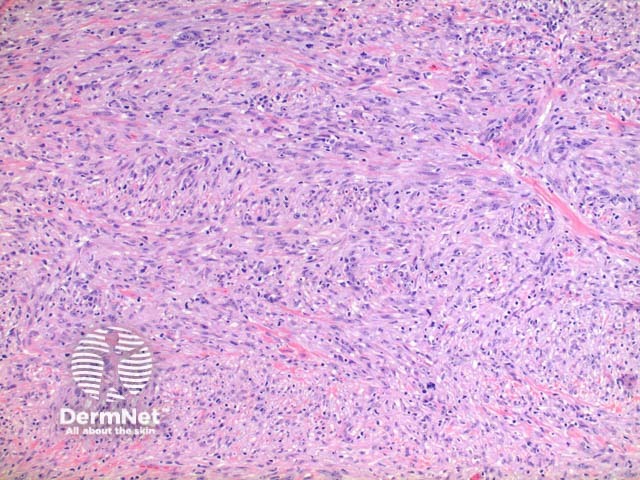

Scanning power view of histology of leiomyosarcoma shows a poorly circumscribed tumour nodule which may be dermal based in the less common dermal leiomyosarcoma (Figure 1) or deeply infiltrating in the subcutaneous form. The tumour is comprised of a spindle cell proliferation forming rough bundles and fascicles (Figures 2 and 3). High power demonstrates spindle cells with cigar shaped nuclei with prominent cytologic atypia and mitotic figures (Figures 4 and 5).

Figure 2

Figure 3